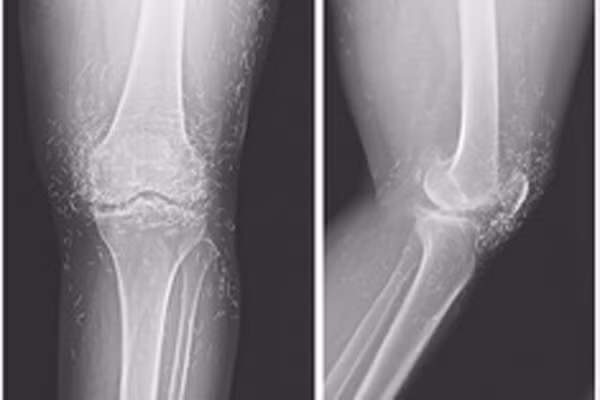

Khi các bác sĩ kiểm tra phim chụp X-quang hai đầu gối của một cụ bà 65 tuổi người Hàn Quốc do bị đau khớp nghiêm trọng, họ phát hiện một "mỏ vàng” là hàng trăm chiếc kim châm cứu tí hon bằng vàng, bị bỏ lại trong mô của bà. Trong quá trình châm cứu cho cụ, các thầy thuốc y học cổ truyền đã cố tình để lại những chiếc kim làm bằng vàng găm trong mô của bà để tiếp tục tạo ra sự kích thích. Tuy nhiên, bác sỹ cho biết, các vật thể lạ bị bỏ lại bên trong cơ thể có thể dẫn tới tình trạng viêm, áp xe và nhiễm trùng. Chúng cũng có thể gây khó khăn cho bác sĩ đọc phim X-quang.